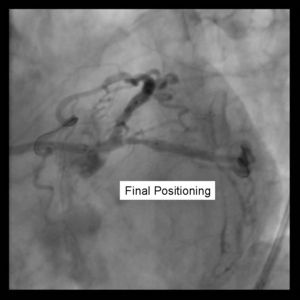

3) Both stents are advanced into the side branch and parent vessel. This may require further predilitation. Generally, the stents are advanced beyond the delivery point. Operator preference differs with respect to amount of overlap. Some operators form a long segment of overlap (>5mm), while others try to minimize overlap. It is absolutely essential that both vessels are covered during the balloon inflation. Optimal placement is ensured by advancing both stents distal to the intended deployment site then pulling them back into position. The proximal marker segements should be aligned, with positional confirmation in at least 2 separate views.

5) Angiography should now be performed to ensure adequate side branch coverage and stent deployment. Distal edge dissections or disease should be addressed before wire removal \

from the vessels.